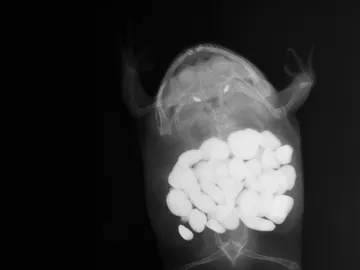

¿Qué objetos extraños pueden llegar a comerse los animales?